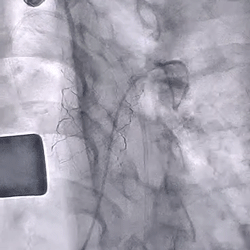

术前造影(可见大量反流) 术后造影(无反流)